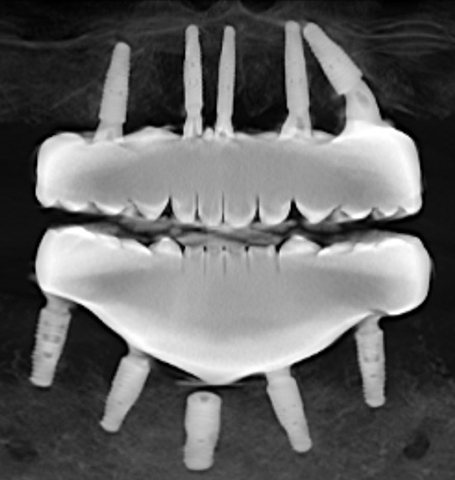

There are several issues with all of the implants, from problems with their locations, problems with mismatched heights from one implant to another, problems with their depth requiring gum grafts as there is no attached gingiva, problems with two of the upper implants apparently touching each other per periodontist report, a few other issues, and all seem to have some level of bone loss around the implants.

All the problems with the implants are creating all sorts of uneven pressures on the implants and my jaws. Implants were carelessly placed haphazardly, then Bansal bragged about how he had never completed a full mouth surgery in such a short amount of time as it took to do my mouth.

All the experts also agreed that the teeth need to be replaced because of the excessive heights and extreme mismatch of the chewing surfaces. Regardless, the teeth need to be redone because implants will be replaced and the screw hole locations will change.

Dental experts opinioned that the All on X that was done to me by Dr Shobhit Bansal is a dismal and unprofessional failure. It's like everything that could be wrong is wrong.

As illustrated earlier in this post, the teeth do not match up which makes it utterly impossible to chew properly. Because they are zirconia, they can not be ground down or modified to enable me to chew even slightly better. Even the slightest amount of grinding will fracture the zirconia.

Also the teeth on each arch are too tall by over 4mm. The teeth hit all the time when I try to talk. The heights of the teeth need to be reduced by at least 4mm on each arch. So we're looking at teeth that are too tall inside my mouth by at least 8mm total. 8mm is 5/16" of an inch. This excessive height also interferes with chewing.

According to the dental experts I consulted, the haphazard placement of the implants that Bansal did creates all sorts of uneven pressures on the implants, the prosthesis, and my jaws. That explains the problems with the temporary prosthesis breaking at the screws, as well as the screws loosening and unusual bone loss at the implants.